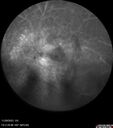

AZOOR - Inactivevaatamisi: 98Sudden vision loss in the left eye 3 years ago. Labs for syphilis, sarcoid and TB all negative. VA 20/32 OD, 20/80 OSveebr 23, 2025